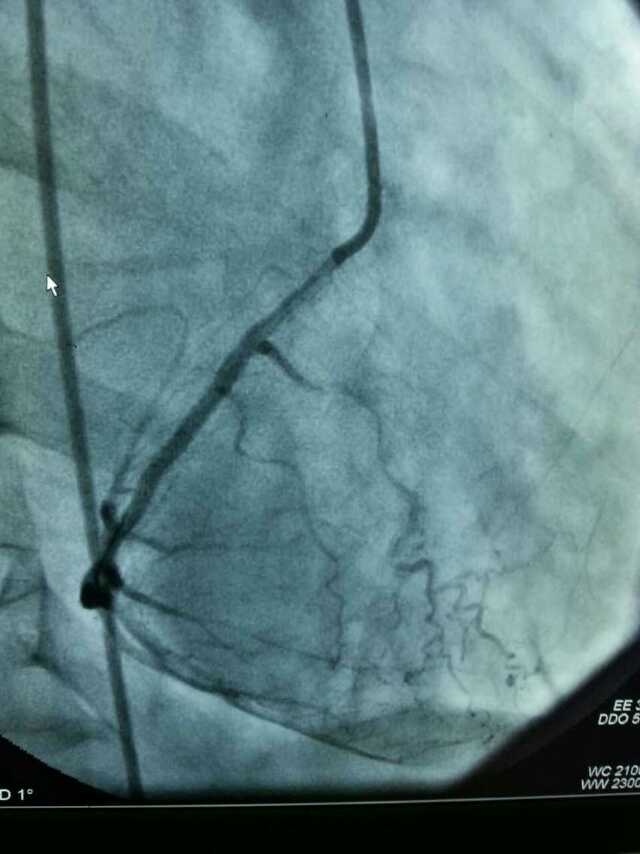

3月20日,家住翔安的庄先生为感谢91club 心血管内科的医护人员在第一时间对他的病情给予明确诊断,并及时采取有效治疗措施,让他的心脏病很快得到康复回家。特地送来一面写着“德医双馨,妙手回春”锦旗以表达他们满满的感激之情。